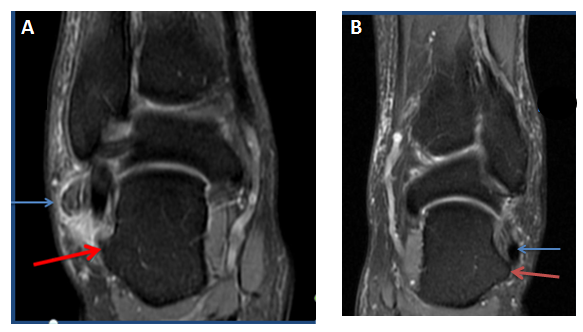

Coronal proton density MRI image of the right ankle showed a hypertrophied peroneal tubercle, it was 11.81 mm high, 5.52mm wide, and 11.20mm AP diameter. A minimal bone marrow oedema was visible in the tubercle. Both peroneal tendons were seen above the tubercle surrounded with soft tissue swelling (Figure 3).

Figure 3 (A) Coronal proton density MRI image of the right ankle shows a hypertrophic peroneal tubercle (red arrow), A minimal bone marrow oedema is seen in the tubercle. Both peroneal tendons are seen above the tubercle surrounded with soft tissue swelling (blue arrow). (B) Left side ankle for comparison shows a prominent hypertrophic peroneal tubercle (red arrow). Peroneal tendons are normal (blue arrow).

The left ankle demonstrated a prominent hypertrophic peroneal tubercle; it was 9.60 mm high, 7mm wide, and has 9.50 mm AP diameter. Peroneal tendons were seen above the peroneal tubercle, they were normal and not surrounded with soft tissue swelling (Figure 3).